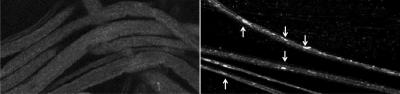

When researchers lowered the amount of presenilin in the neurons of fruit fly larvae, less GSK-3ß became activated and vesicles began speeding along cells in an uncontrolled manner.

Decreasing levels of both presenilin and GSK-3ß at once made things worse, resulting in "traffic jams" as the bubbles got stuck in neurons.

Dyneins carry vesicles toward the cell nucleus, while kinesins move in the other direction, toward the periphery of the cell. When all is well and GSK-3ß levels are normal, both types of motors bind to vesicles in carefully calibrated numbers, resulting in smooth traffic flow along neurons.

When GSK-3ß levels are high, too many motors attach to the vesicles, leading to slow movement as motor activity loses coordination. Low GSK-3ß levels appear to have the opposite effect, causing fast, uncontrolled movement as too few motors latch onto vesicles.

Both scenarios — too much GSK-3ß or too little — can result in neuronal blockages.